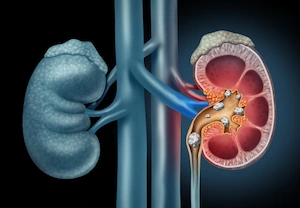

سنگ شکنی حالب فوقانی، میانی و تحتانی تا ۴۶ میلی متر

یک نکته بسیار حیاتی که مرکز دکتر فرهادی را از تمام ایران متمایز می کند، قدرت دستگاه و مهارت ایشان در درمان سنگ های بزرگ است. در حالی که در اکثر مراکز سنگ شکنی کشور، درمان سنگ کلیه و سنگ حالب فوقانی فقط تا ۲۰ میلی متر امکان پذیر است، در کلینیک دکتر اصغر فرهادی در مشهد، سنگ های بسیار بزرگتر نیز با موفقیت توسط دکتر اصغر فرهادی درمان می شوند.

ما مفتخریم اعلام کنیم که درمان سنگ های حالب فوقانی، حالب میانی و حالب تحتانی تا ابعاد خیره کننده ۴۶ میلی متر با موفقیت کامل در این مرکز درمان می گردد. این موفقیت مرهون ۳۵ سال تجربه تخصصی دکتر اصغر فرهادی و انجام بیش از ۶۰۰۰ سنگ شکنی موفق است. در واقع در این مرکز محدودیتی در زمینه محل سنگ شامل کلیه ها ، حالب و مثانه وجود ندارد.

سنگ شکن حالب فوقانی در مرکز دکتر فرهادی

درمان سنگ های حالب فوقانی حساسیت بسیار بالایی دارد. استفاده از دستگاه های قدیمی ممکن است باعث جابجایی سنگ یا آسیب شود. اما در اینجا، تمام مراحل توسط شخص دکتر اصغر فرهادی انجام می شود. نظارت مستقیم ایشان از مرحله ویزیت تا دفع کامل سنگ، تضمین کننده سلامت شماست.

سنگ شکن حالب تحتانی: پایان دردهای جانکاه

سنگ های حالب تحتانی معمولاً با دردهای انتشاری به لگن و سوزش شدید همراه هستند. به دلیل نزدیکی به مثانه، بسیاری از مراکز جراحی را پیشنهاد می دهند. اما در کلینیک ما، سنگ مثانه ۱۱ میلی متری و سنگ های حالب تحتانی با بالاترین درصد موفقیت و بدون جراحی خرد می شوند.